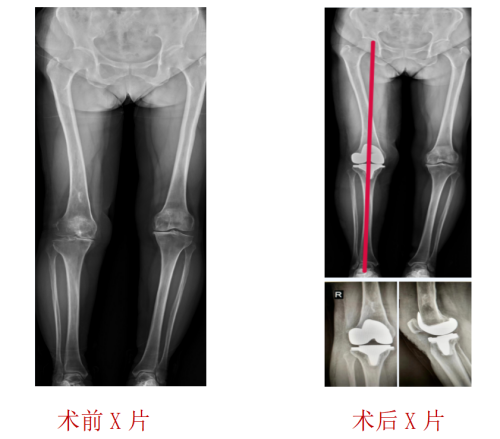

运动医疗、关节骨病科主任、主任医师丑克了解到,对平时走路散步时的疼痛程度张阿姨还能忍受,但是上下楼梯或者爬山、下蹲时就会明显感觉疼痛加重,只有休息后症状才能稍减轻,以前年轻时还有过右股骨下段化脓性骨髓炎病史,导致股骨畸形。医生经过仔细体格检查并结合影像学检查结果,诊断张阿姨患上的是“右膝关节退行性病变”。因张阿姨既往有过化脓性骨髓炎,为提高治疗效果,运动医疗、关节骨病科医护团队为张阿姨制定了个性化的手术治疗护理方案,术中使用IKPAS全膝关节导航定位技术,不开髓,减少手术创伤,精准定位截骨为张阿姨完成全膝关节置换手术。

“IKPAS全膝关节手术定位系统利用传感器技术,不依赖术前患者的影像数据,通过陀螺仪及加速度计配合特定的算法,在术中实时测量股骨远端与胫骨平台的截骨角度,计算获得个性化的角度数据,以辅助医生更加精准地完成膝关节置换手术中下肢力线测量和截骨定位,被称之为智慧型膝关节置换手术。”丑克主任介绍,该定位系统可用于初次和复杂膝关节置换手术,与传统的关节置换手术相比,智慧型膝关节置换术将误差控制在1°以内,具有不需打开髓腔、减少术中术后出血、提高截骨精准度、缩短手术时间、有效降低并发症发生等优势,而且在不改变医生手术习惯和操作流程的基础上,达到了轻、快、准的微创治疗要求。

丑克主任表示,因患者有过化脓性骨髓炎导致股骨侧畸形,不适合常规的开髓定位,使用IKPAS全膝关节手术定位系统可实现不开髓手术,且有效减少术中术后出血,实现手术微创化、精细化,避免骨髓炎的再次发生。智能化手术的实施不但提升了关节骨科医疗技术水平和手术疗效,也为骨关节病患者实现更标准、更规范、更安全的治疗提供了多种选择。